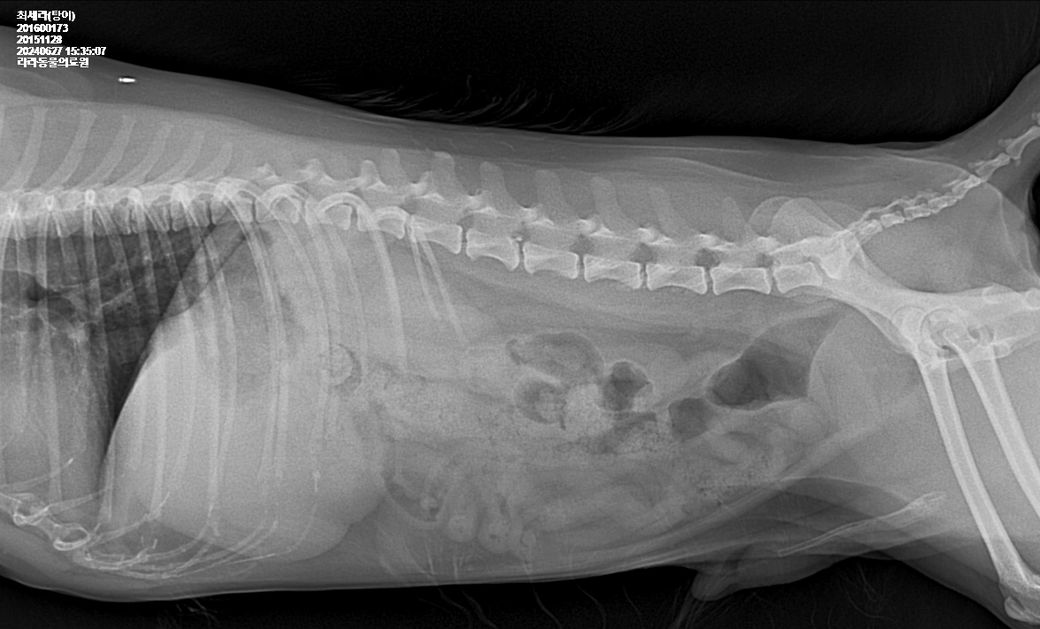

엑스레이도 찍었는데 엑스레이로는 안보이는것같아요